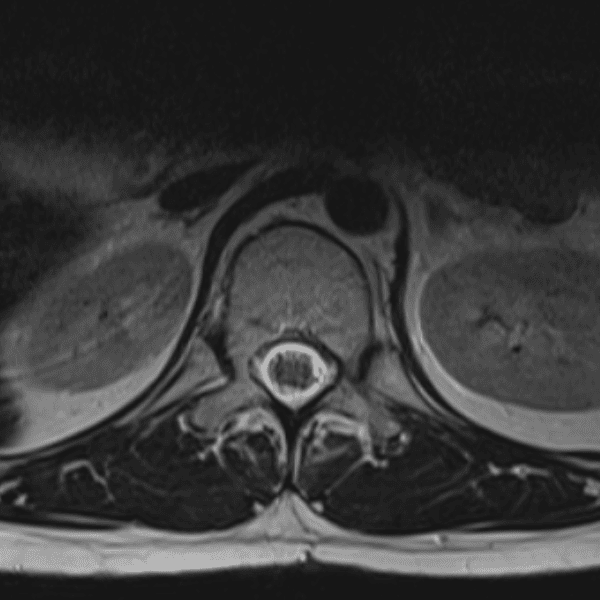

Simulates call by including subtle or difficult cases and some normals.

35 cases